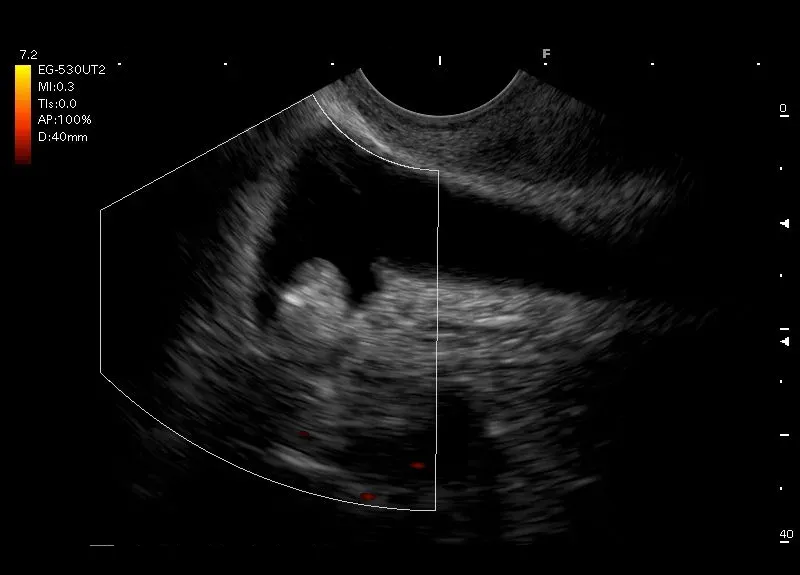

Pogrubienie ściany pęcherzyka żółciowego zawierające w ścianie torbiele, złogi cholesterolowe lub niewielkie przestrzenie bezechowe - adenomiomatoza pęcherzyka żółciowego